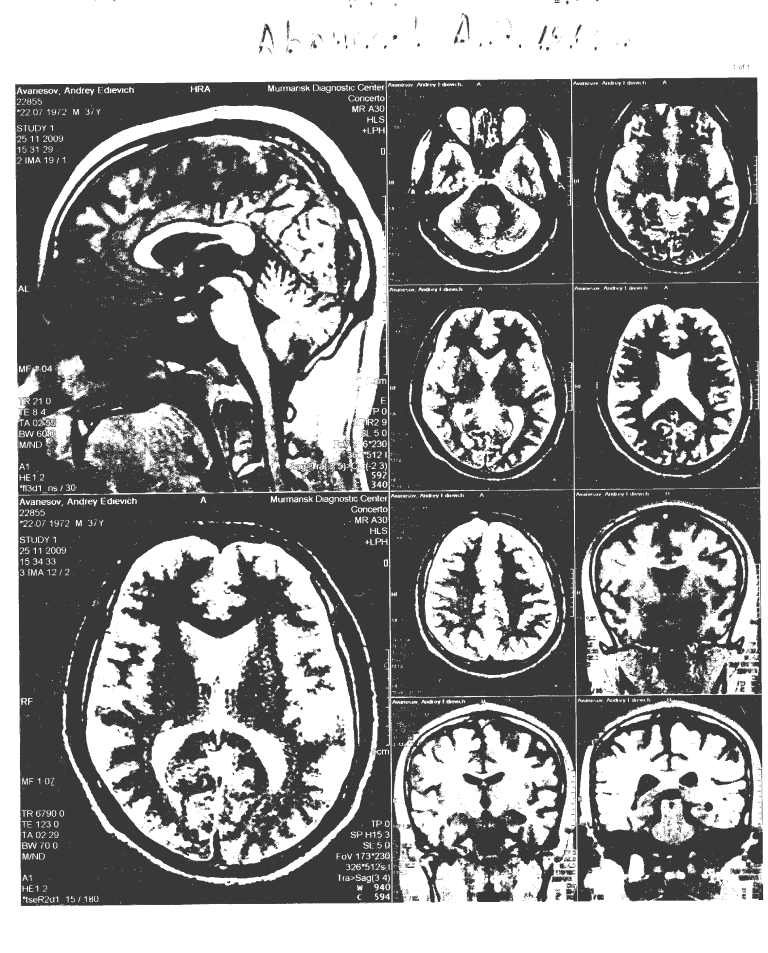

Вопрос:   Доброго времени суток! Дополняю свои вопросы № 2543 и № 2551 снимками МРТ. Очень прошу их прокомментировать, надеюсь, качество снимков достаточное. Заранее благодарю за помощь.

Файл с дополнительной информацией

Ответ:   Такое качество снимков не приемлемо, это скорее художественная графика. Чтобы МРТ-снимки были читабельны необходимо их сфотографировать на негатоскопе фотоаппаратом хорошего разрешения.

Автор ответа:   Камбиев Ренат Леонидович